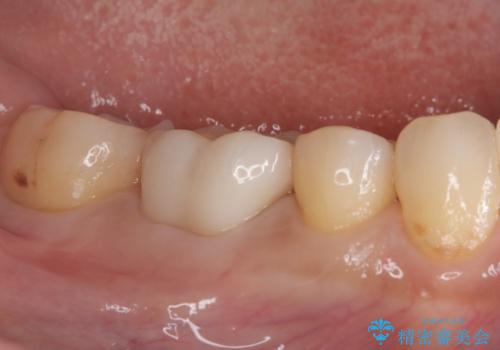

ズキズキ痛い歯 オールセラミッククラウンによる修復

- 冷たいもので長引く痛みがあることを主訴に来院されました。

抜髄を行い、オールセラミッククラウンにて修復を行いました。

根管充填はバイオセラミックシーラーを使用しています。